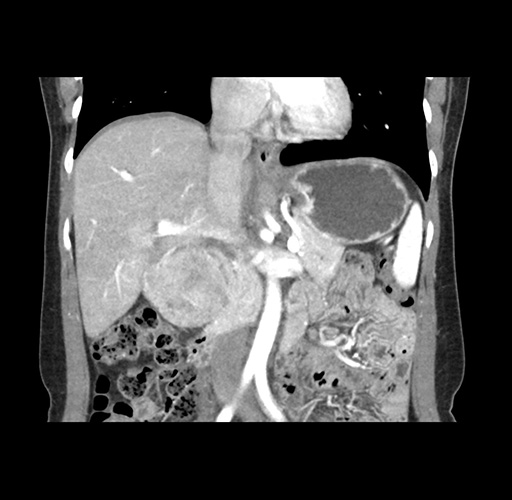

Imaging Analysis

Look through the patient's CT scan to identify any areas of concern for the necessary procedure.

Based on your CT findings, which issue(s) would give reason for "planned slowing down moment(s)" in this case?

Considering a standard left lateral sectionectomy procedure, what step(s) of the operation would you do differently in this case ?